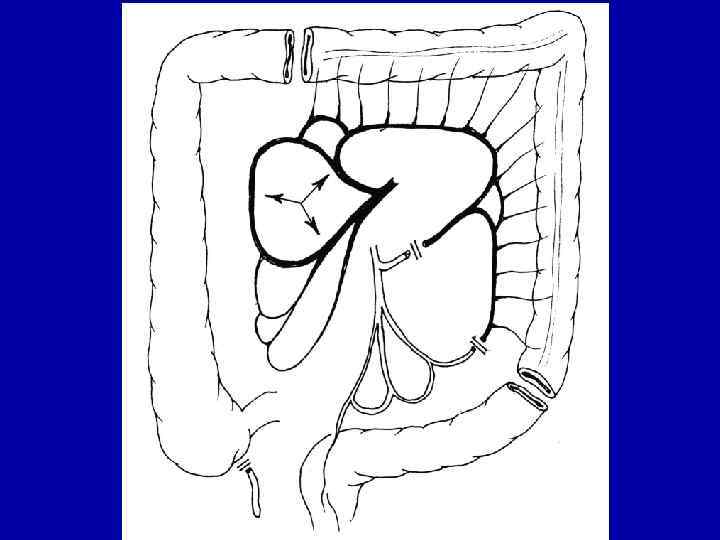

Схема субтотальной загрудинной колоэзофагопластики

Схема заднемедиастинальной эзофагопластики толстой кишкой